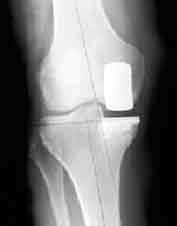

Post-operative View with Implant